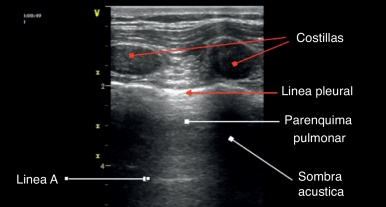

En general el aire es un “enemigo del ultrasonido”, en el sentido de que produce una gran atenuación del haz de ultrasonido por lo que dificulta la adecuada visión de estructuras. Como los pulmones están llenos de aire, técnicamente uno “no ve” los pulmones sino que los artefactos de las demás estructuras. Por lo tanto, la interpretación que se le da a las imágenes del ultrasonido pulmonar es la interpretación de los artefactos que se producen al hacer el examen (figura 1):

- Las estructuras más superficiales (piel, celular subcutáneo, músculos pectorales e intercostales) conducen bien las ondas de ultrasonido y no generan artefactos.

- Las costillas bloquean la transmisión de las ondas, apareciendo brillantes hacia el lado superficial y generando sombra acústica hacia lo que está detrás de ellas.

- Las pleuras parietal y visceral aparecen como una línea hiperecoica (brilla), que se desliza de lado a lado de la pantalla, lo que representa el movimiento de las superficies pleurales entre sí de acuerdo a la expansión y retracción pulmonar al ventilar.

- El parénquima pulmonar normal no se ve (está lleno de aire, que dispersa las ondas de ultrasonido).

La flecha amarilla en la imagen indica una línea hiperecogénica, la llamada línea pleural, que representa la zona de contacto entre las pleuras visceral y parietal.

Las flechas blancas representan las líneas A, que son artefactos de reverberación de la línea pleural hacia el infinito. Las líneas A siempre mantienen más o menos la misma distancia entre sí, que corresponde a la distancia entre el transductor a la línea pleural. La presencia de líneas A no tiene valor patológico.

Por lo tanto, una imagen normal al ultrasonido pulmonar (bien tomada, en un campo entre 2 costillas) consiste en la apreciación de la línea pleural con su correspondiente lung sliding, las costillas producirán sombra acústica, y el parénquima pleural se verá algo moteado, con líneas A (figura 7). A esta visualización también se le conoce como el signo del murciélago (figura 8).